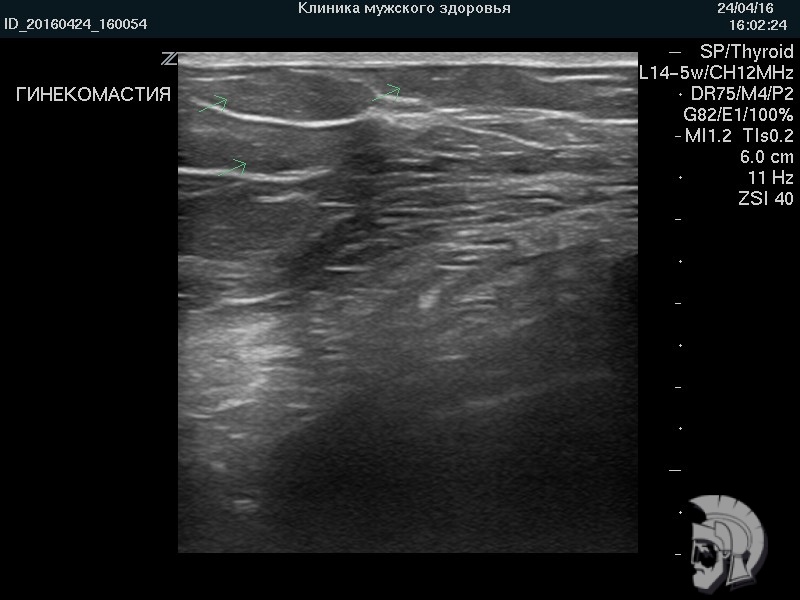

Фото гинекомастии.

На фоне мышц (представлены длинными продольными волокнами) определяются крупные жировые дольки (указаны стрелками) |